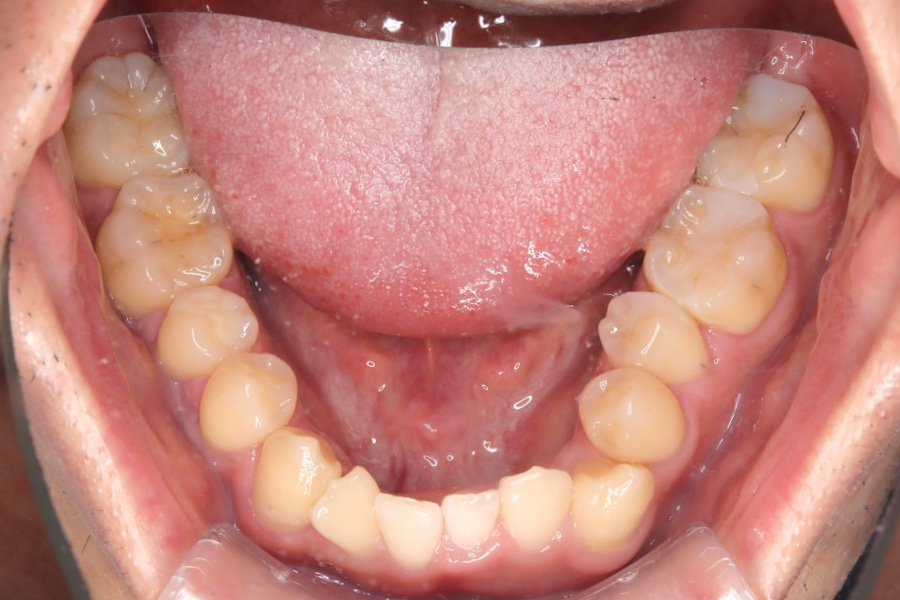

治療後

主訴 歯のガタつき

期間 2年

治療内容 インビザライン矯正

非抜歯

治療に伴うリスク 矯正終了後は、リテーナーを指示通りに使用し、歯の後戻りを防ぐ必要があります。